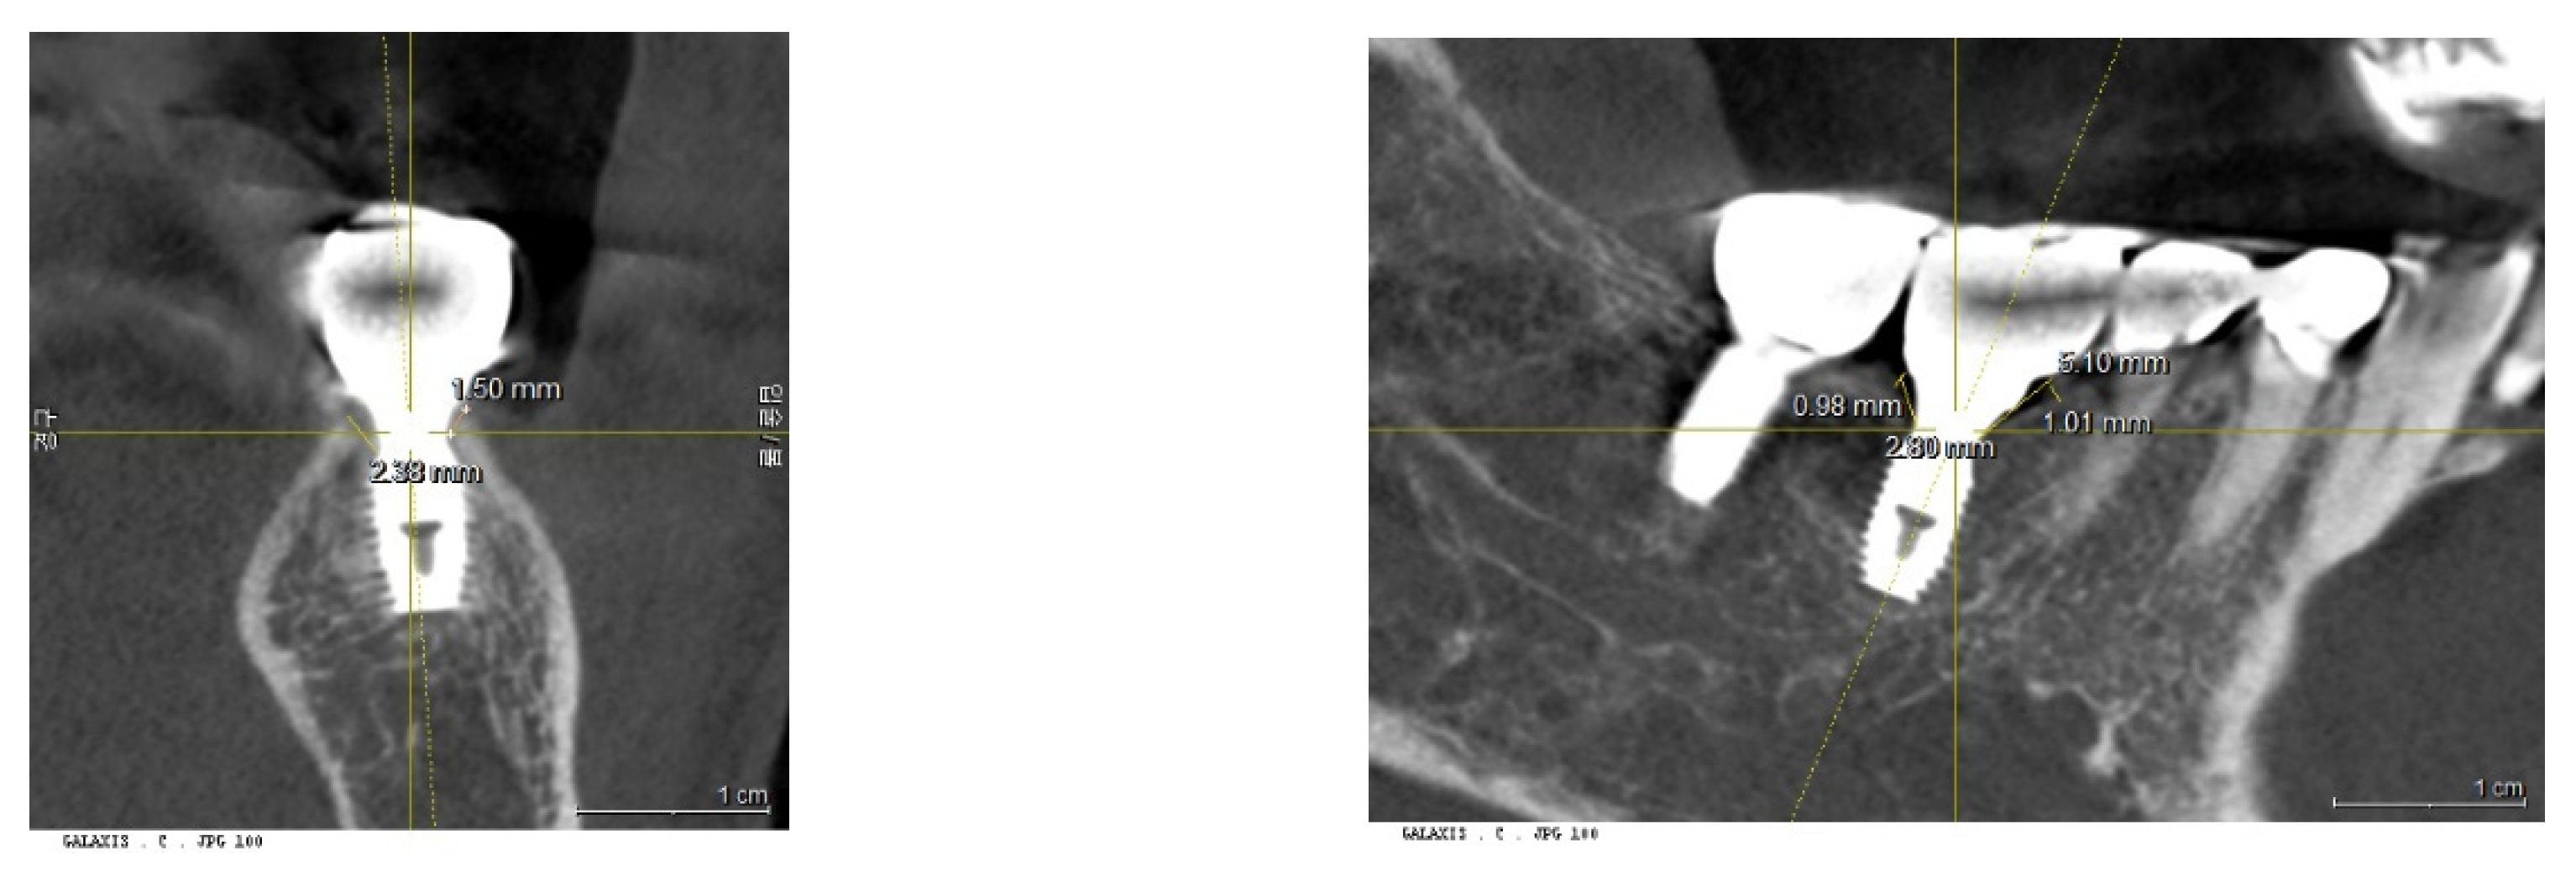

Measurements from the panoramic views and CBCT were conducted using Sirona Dental Systems (Device: XIOX Plus ORTHOPHOS_XG_3D; Programs: SIDEXIS, GALILEOS Implant Viewer; Version 1.9.5605.25519 ID7).

Calibration of CBCT: To ensure accuracy, the presentation plane of the CBCT was centered around the long axis of the fixture. This allowed for the confirmation of the fixture's size—both diameter and length—against its known original dimensions.

Figure 11. Calibration of CBCT Images. This figure demonstrates the calibration process where images are coordinated along the long axis of the fixtures. This alignment is crucial for accurate measurement and analysis, ensuring that the fixture dimensions are accurately reflected in the CBCT images.

2. Measurement of Placement Depth (PD) from CBCT - 3DSTA

Placement depth was assessed using CBCT in the 3DSTA context, focusing on both the central and peripheral areas in mesiodistal and buccolingual aspects:

a) Central Placement Depth (cPD): - The depth at the central area was measured as the perpendicular distance from the top point of the crestal bone to the platform of the implant fixture at its most outer point (e.g., at the 5 mm point of a 5 mm diameter fixture).

b) Peripheral Placement Depth (pPD) - Mesiodistal and Buccolingual Aspects: - In the mesiodistal aspect, the depth was measured as the perpendicular distance from the top point of the crestal bone to the platform of the implant fixture at the most outer point of the crown. - In the buccolingual aspect, the depth was measured from the most coronal top point of the crestal bone to the platform of the implant fixture.